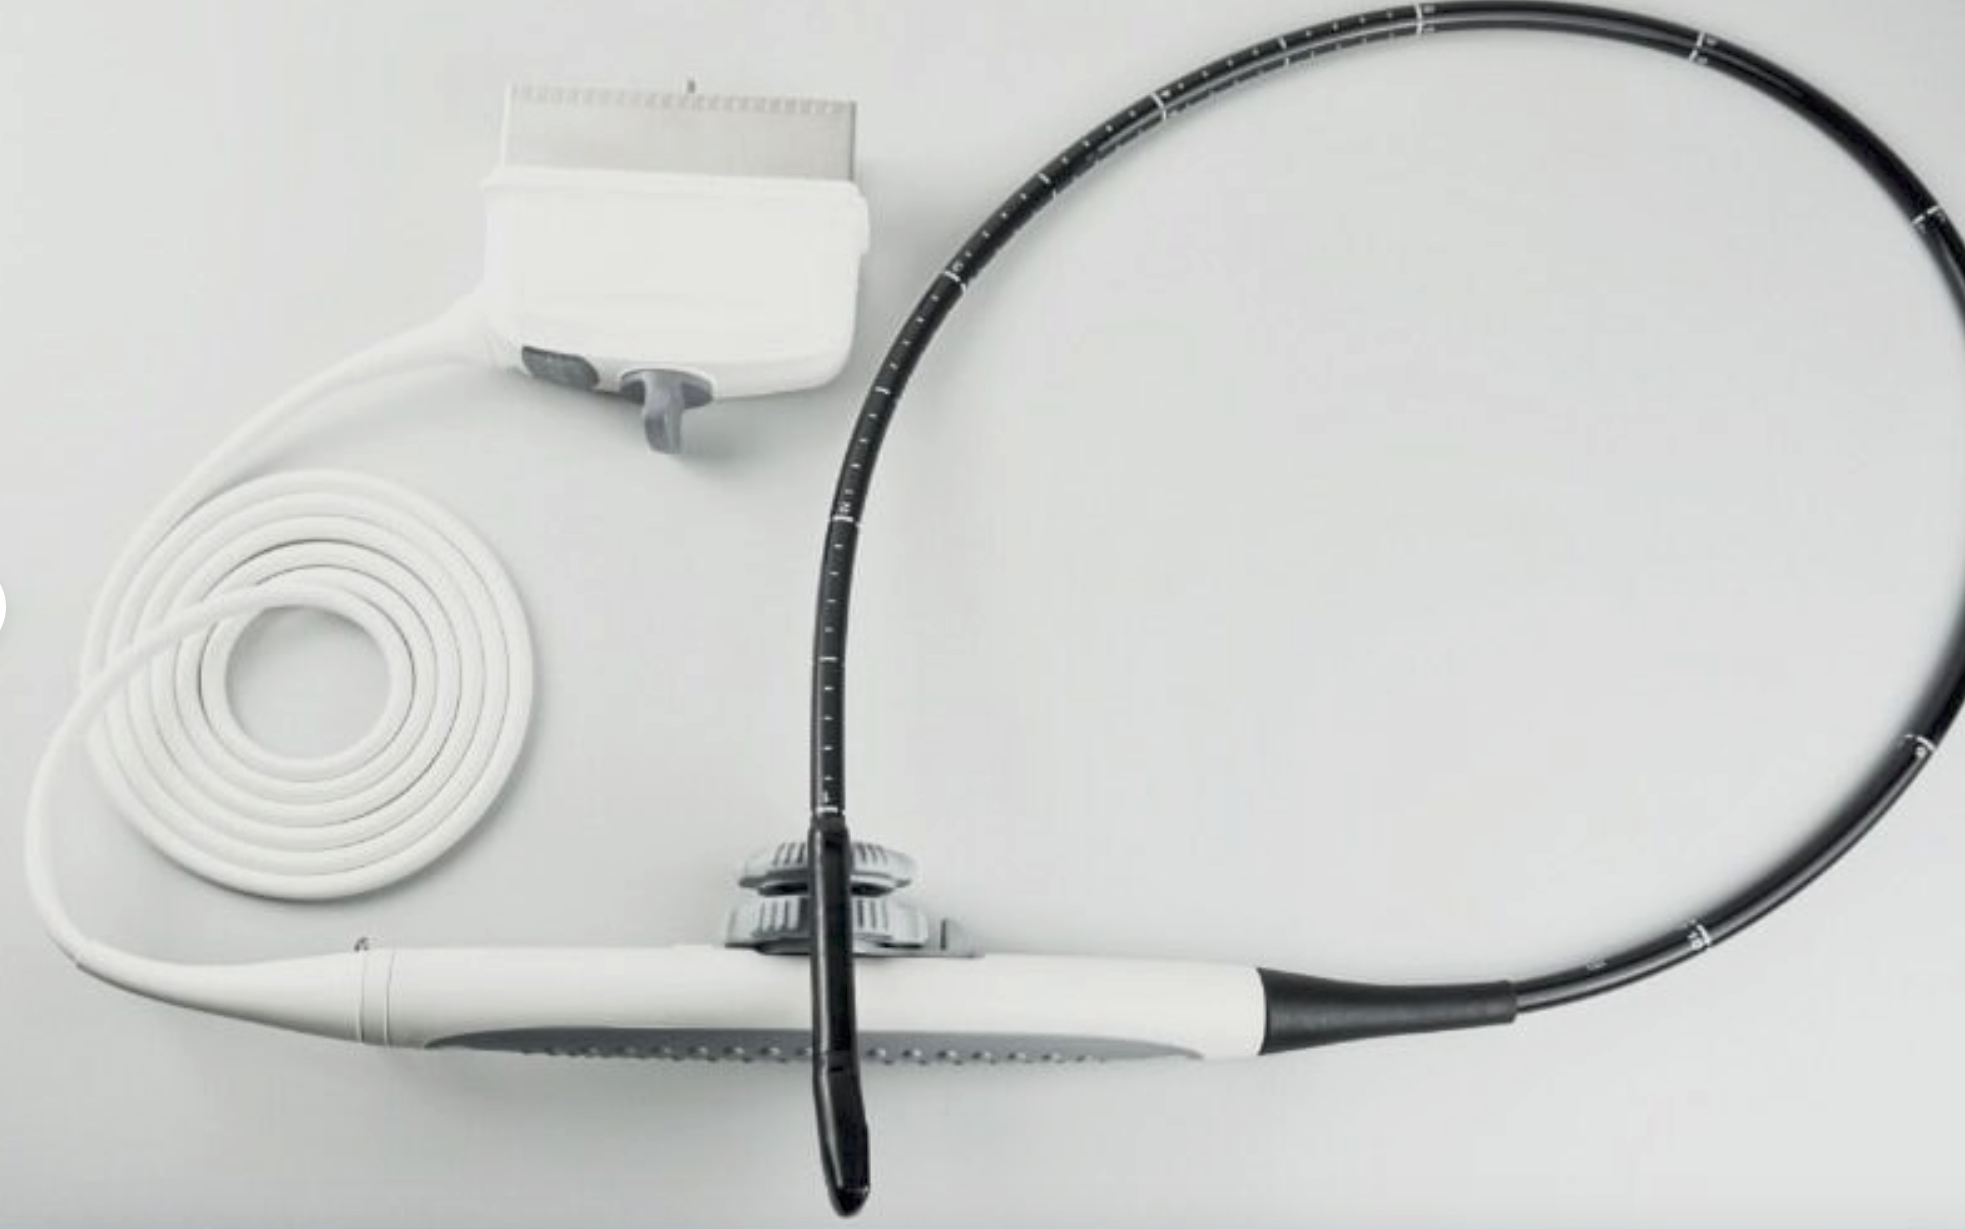

SONOSITE L25X LINEAR FOR M-TURBO EDGE S - Top-Notch Ultrasound Probe

SONOSITE L25X LINEAR FOR M-TURBO EDGE S-NERVE TRANSDUCER - Ultrasound Probe

The SONOSITE L25X LINEAR FOR M-TURBO EDGE S is a premier ultrasound transducer designed to provide high-quality imaging for a variety of clinical applications. This specialized probe is compatible with the SONOSITE M-TURBO EDGE system, a leading point-of-care ultrasound device that delivers exceptional image clarity and reliability. Whether you are in emergency medicine, regional anesthesia, or vascular procedures, the SONOSITE L25X LINEAR provides precise and reliable results every time.

Designed with advanced technology, the SONOSITE L25X LINEAR FOR M-TURBO EDGE S offers a frequency range that is optimal for superficial imaging, aiding healthcare professionals in obtaining detailed and accurate images. The probe's ergonomic design ensures ease of use during extended scanning sessions, reducing operator fatigue. SONOSITE, a brand known for its innovation and quality, ensures that every detail of the L25X LINEAR is tailored to meet the high demands of modern medical environments.

In addition to its superior imaging capabilities, the SONOSITE L25X LINEAR FOR M-TURBO EDGE S is built to withstand the rigors of everyday clinical use. Its durable construction means it can handle frequent cleaning and disinfection processes essential in maintaining hygiene standards in medical settings. Investing in this ultrasound probe not only enhances diagnostic accuracy but also ensures a reliable performance that stands the test of time.

The SONOSITE L25X LINEAR FOR M-TURBO EDGE S is also known for its quick-and-easy setup, which saves valuable time in fast-paced clinical settings. Furthermore, it offers seamless integration with the SONOSITE M-TURBO EDGE system, providing a user-friendly experience that complements the workflow of healthcare professionals. This leads to improved patient care and optimized clinical operations.

For any healthcare facility looking to enhance its ultrasound imaging capabilities, the SONOSITE L25X LINEAR FOR M-TURBO EDGE S is a worthy investment. Its high-resolution imaging, durability, and user-oriented design make it a standout choice in the market. With the SONOSITE L25X LINEAR, clinicians can perform accurate diagnoses, carry out intricate procedures with confidence, and ultimately, improve patient outcomes. Don't miss out on the opportunity to advance your practice with this exceptional ultrasound probe.